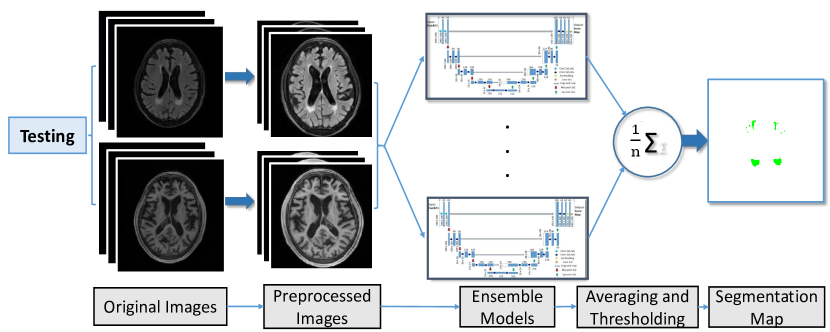

As shown in Figure 5, U-Net models with same architecture are trained with random parameter initialization and shuffled data in the batch learning. For each of the U-Net models, when given a test image, a probability segmentation map will be generated by that model. Then the resulting maps will be averaged. Finally an empirically-picked threshold will be used to transform the scores map into a binary segmentation map.